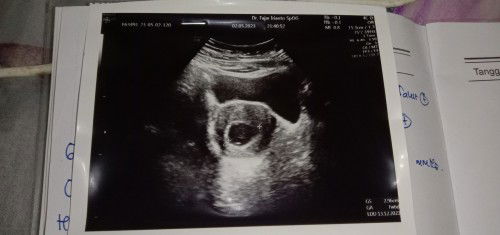

Assalamualaikum bunda"aku mau cerita Hpht tanggal 21 Februari dan aku telat haid 5 hari dibulan Maret aku testpack hasilnya garis 2 terang , tapi aku tidak langsung pergi ke dokter, aku pergi ke dokter dibulan Mei tanggal 2 tapi ketika di USG baru terlihat kantung nya saja dan kata dokter nya tidak apa"dan disuruh balik 10 hari lagi. Aku jga dikasih obat penguat kandungan dan vitamin. Tanggal 5 Mei kemaren aku dirumah aku ada posyandu dan aku disuruh pergi kesna, dan ketika aku pergi diperiksa aku blng ke bidannya bahwa baru terlihat kantung nya saja tetapj bidannya malah menyuruh aku berbaring dan perut aku di pencet" dan dia blng "iyaa ini blm ada janinnya dan kemungkinan hamil BO" aku shock dan kesal mendengar bidan ngomong seperti itu padahal dokter saja tidak ada bicara seperti itu. Ketika perut aku dipencet"aku khawatir takut terjadi hal yang tidak diinginkan Dan benar saja pagi ini aku keluar flek coklat dan ada sedikit gumpalan, aku takut kenapa"sama calon anak aku karena dipencet"dengan bidan perutnya. Karena sebelumnya aku tidak mengalami flek sama sekali.🥺#bantusharing #ingintahu #firstmom